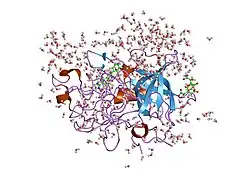

Urokinase is a 411-residue protein, consisting of three domains: the serine protease domain (consisting of residues 159–411), the kringle domain (consisting of residues 50-131), and the EGF-like domain (consisting of residues 1-49). The kringle domain and the serine protease domain are connected by an interdomain linker or connecting peptide (consisting of residues 132–158). Urokinase is synthesized as a zymogen form (prourokinase or single-chain urokinase), and is activated by proteolytic cleavage between Lys158 and Ile159. The two resulting chains are kept together by a disulfide bond between Cys148 and Cys279.[9]